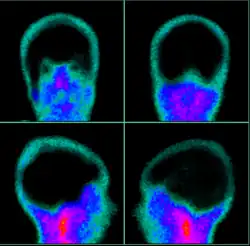

| Exame de cintilografia cerebral sem perfusão, corroborando o diagnóstico de morte encefálica (ME) | |

- Cintilografia cerebral afere a perfusão segundo a emissão radio ativa de isotopos de elementos pesados (Tecnécio 99, Molibdênio 98)

Cintilografia cerebral. Evidente ausência de perfusão da massa encefálic